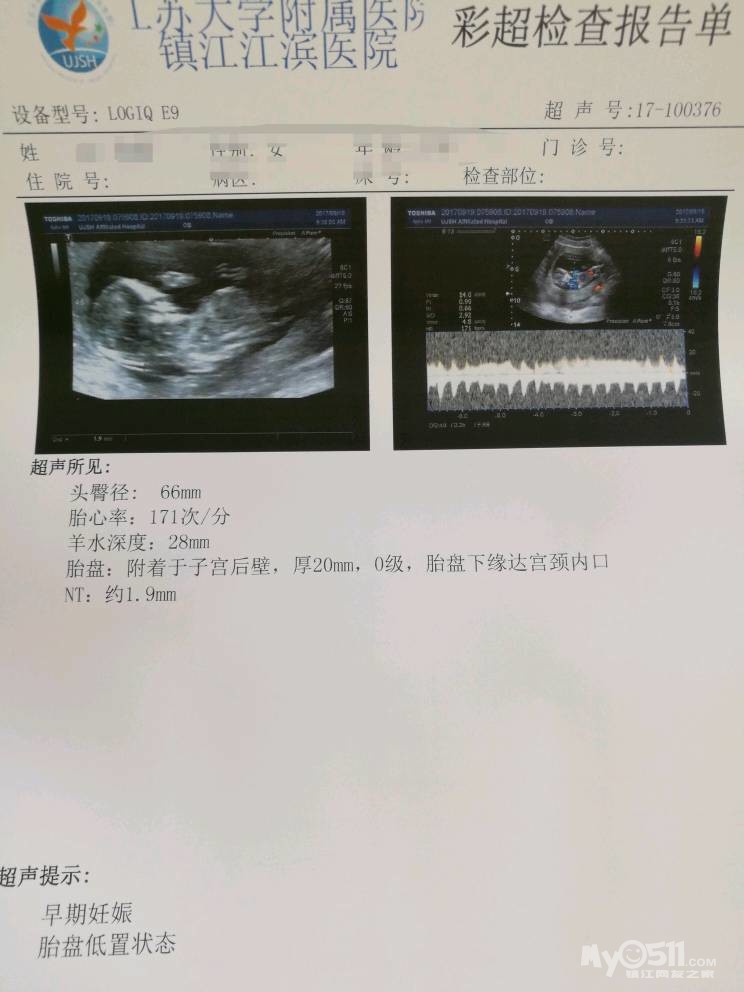

先上一张NT照镇楼,待我空了来慢慢码字

照片忘了传了,补上来

第一次去产检做了NT医生说胎盘有点低,把我还小紧张了一下,医生嘱咐要多休息,别再抱老大了,不见红都没问题,后期会自己长上去的。好在老大很懂事,每次在外面玩得累了想要我抱着,只要告诉她妈妈现在肚子里有小宝宝了,不能再抱你了,会压到宝宝的,她再累也能自己坚持走回家

因为怀孕前期做B超查出来胎盘很低,所以今天去做三维彩超特意问了医生长上来没有,结果长是长了,就是还不达标呢

说是要距离宫颈口20mm才算是安全范围之内。我还差4mm,不知道后期会不会继续往上长啊?